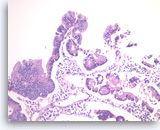

Ductal adenocarcinoma #3,

Pancreas FNA, Cell Block.

The tumor cells form glandular structures with focal loss of cell polarity and stratification. There are also scattered single and small groups of tumor cells. Intracytoplasmic mucin is seen in some of the tumor cells. Note extracellular mucin (right edge) and a background of necrotic cellular debris.

40X

Ductal adenocarcinoma #3,

Pancreas FNA, Cell Block.

The tumor cells form glandular structures with focal loss of cell polarity and stratification. There are also scattered single and small groups of tumor cells. Intracytoplasmic mucin is seen in some of the tumor cells. Note extracellular mucin (right edge) and a background of necrotic cellular debris.

40X